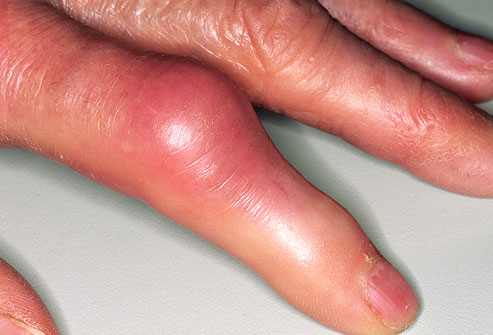

痛风的症状之手指

尿酸在手指肿沉积便可累及手指。在痛风发作时关注不要过多活动以缓解疼痛。